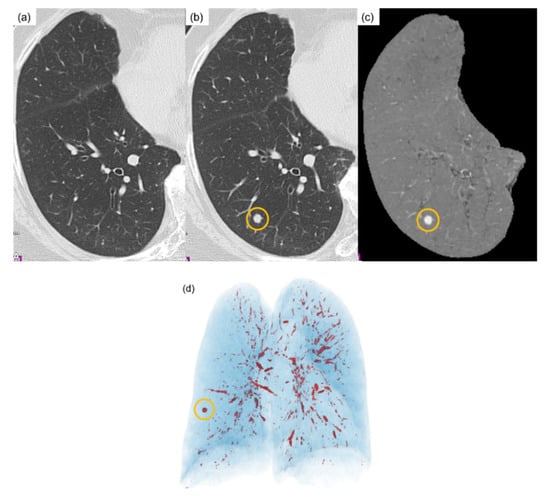

3.1. Temporal Subtraction Technique with Deep Neural Network

4.2. Results and Evaluation